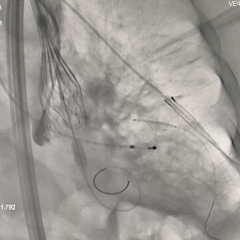

左冠提前预埋冠脉导丝

根部造影

可见明显反流,瓣叶活动度不佳

导丝顺利跨瓣

20mm球囊预扩

无腰无漏,右冠显影正常;RN侧钙化融合推挤球囊贴靠左窦侧,可见左冠显影欠佳,考虑有球囊贴靠STJ的原因,决定预埋支架保护再准备瓣膜释放